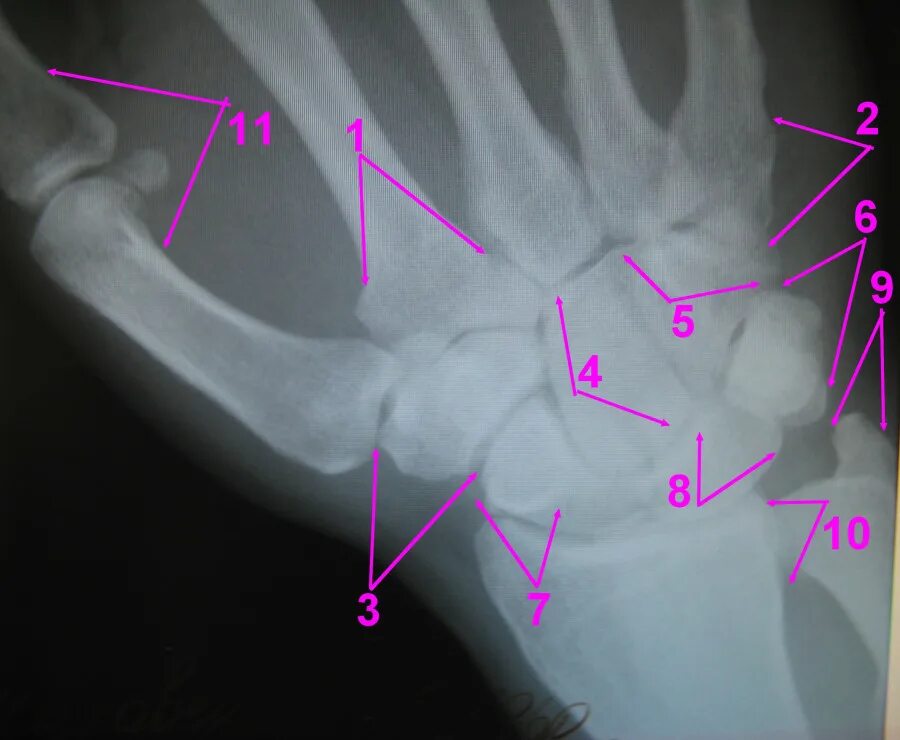

Перелом пястной кости код мкб 10